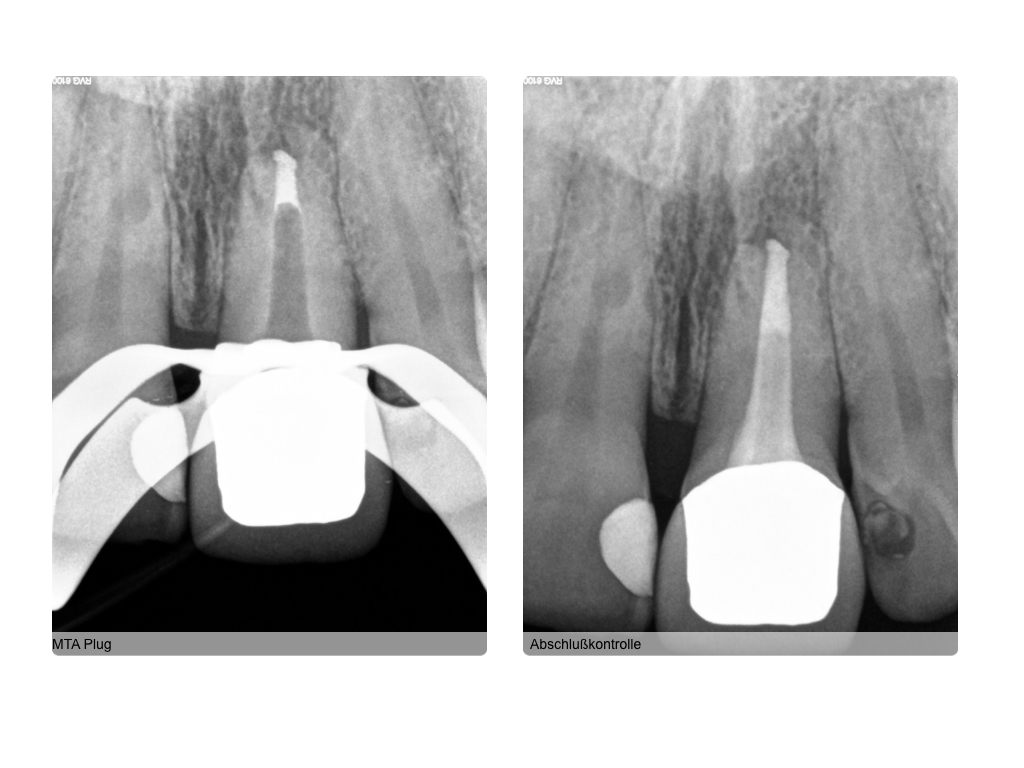

WS 04082016.005 Veröffentlicht 2. August 2016 am 1024 × 768 in Zustand nach traumatischer Zahnverletzung mit nachfolgender Wurzelbehandlung und Wurzelspitzenresektion